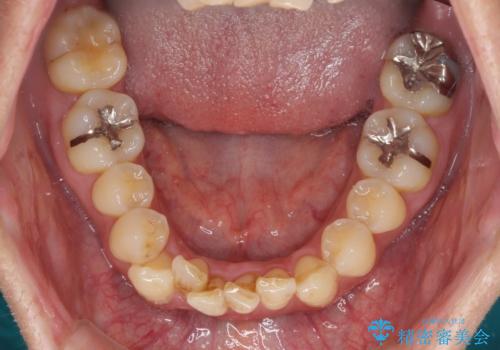

前歯のデコボコ ワイヤー装置での短期間治療

- 前歯のデコボコを気にして来院された患者様です。

インビザラインまたはワイヤー装置、どちらでも対応可能でしたが、自己管理の少なさ、期間の短さから、ワイヤー装置による矯正治療を行うこととしました。

治療開始の頃は、食事や歯磨きが慣れず、装置が頻繁に脱落しましたが、2,3ヶ月ほどで慣れ、その後は1年ほどで治療を終えることができました。